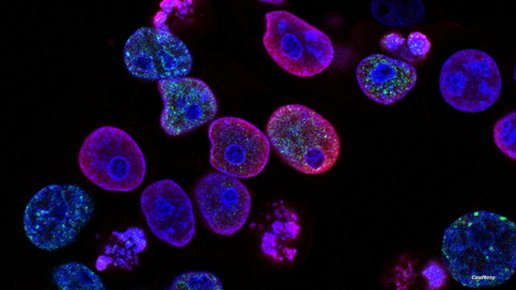

اللقاح المنتظر "قيد التطوير حاليا"، ومن شأنه تدريب الجسم على التعرف على السرطانات ومهاجمتها باستخدام تقنية mRNA.

والحمض النووي الريبوزي المرسال" أو (mRNA)، هو جزيء ينقل الشفرة الجينية من الحمض النووي إلى الخلية لتنتج بروتينات، ويقوم بإرسال تعليمات لداخل الخلية وستكون مهمته في هذه الحالة "تدمير الخلايا غير الطبيعية أو السرطانية" وبالتالي يقوم الجسم بمهاجمتها.

ويمكن استخدام نهج اللقاح الفردي لضمان تلقي المرضى "لقاحات ضخصية ومخصصة" بعد الجراحة مباشرة، ويتم بعد ذلك "تحفيز استجابة مناعية بحيث يمكن للخلايا التائية في جسم المريض فحصها، وفقا لما ذكره القائمين على تطوير اللقاح المنتظر.

ويطلق على الخلايا التائية اسم "الخلايا القاتلة الطبيعية"، وهي خلايا الدم البيضاء المشاركة في استجابات المناعة الفطرية والمناعة المكتسبة أيضا، وفقا لمعهد "Bioscience".

وتدافع تلك الخلايا عن الكائن ضد الأخطار الخارجية مثل "الفيروسات والبكتيريا"، والداخلية مثل "الخلايا السرطانية"، وتلعب دورا مهما، في مهاجمة الخلايا المصابة بـ"فيروس أو خلل وظيفي والتي يمكن أن تكون ورما".